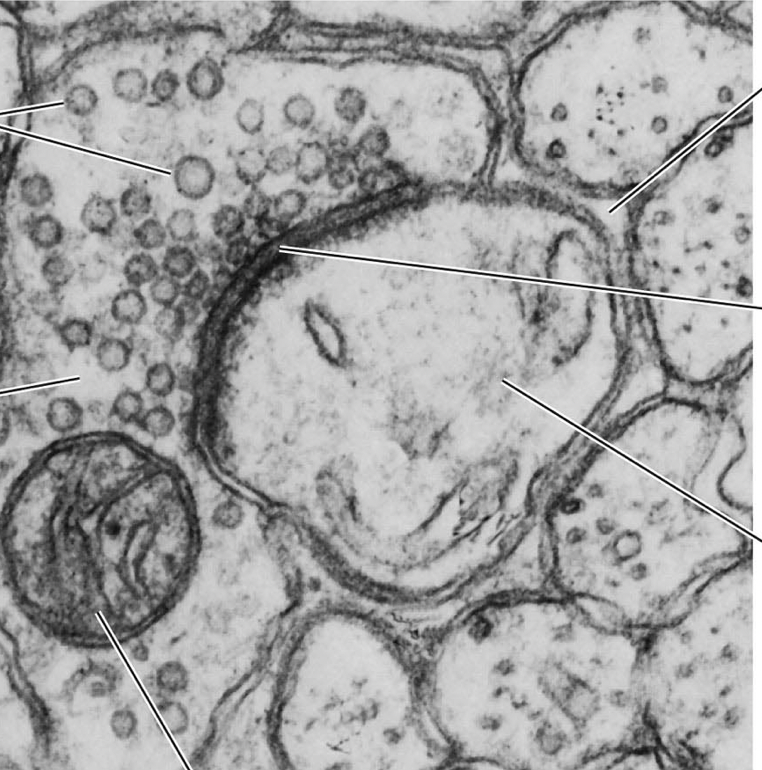

steps for NT release